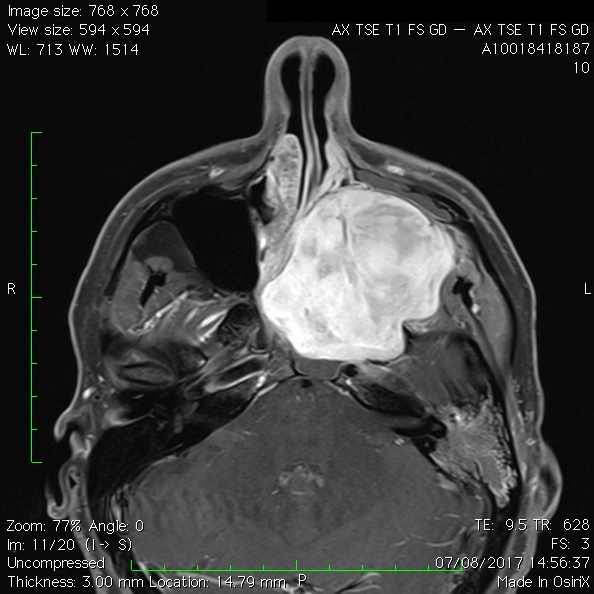

Les neurinomes de l’acoustique

Ce sont des tumeurs bénignes à croissance lente développées au dépens du nerf vestibulaire reliant l’oreille au cerveau. Aussi appelé schwannomes vestibulaires, ces tumeurs peuvent croître et endommager le tronc cérébral et les nerfs crâniens adjacents lors de leur développement. Les symptômes comprennent des troubles de l’équilibre ou des instabilités, une perte auditive et/ou des bourdonnements (acouphènes) dans l’oreille affectée.

Le traitement comprend la surveillance radiologique, la chirurgie ou la radiothérapie stéréotaxique. La chirurgie est réalisée par les membres de l’équipe du service ORL spécialisés dans cette chirurgie. Ensemble, ils décident de la meilleure façon d’aborder et enlever la tumeur tout en préservant la fonction nerveuse du visage. Un surveillance de la de la fonction du nerf faciale (monitoring) est effectuée pendant toute la durée de la chirurgie.

Une autre option de traitement réside dans la radiochirurgie stéréotaxique, un type de radiothérapie qui peut concentrer les rayons X à haute puissance sur la tumeur.

Différents stades du neurinome (d’après Jackler, ATLAS OF SKULL BASE SURGERY & NEUROTOLOGY. Thieme. ©2009)